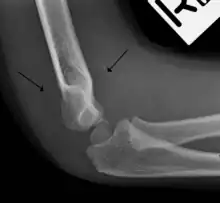

Fat pad sign: Ventral fat pad bowed and dorsal fat pad visible in a case of a nondisplaced fracture of the radius head which is not visible directly.

Anterior sail signs as well as posterior fat pad in a child with a supracondylar fracture.